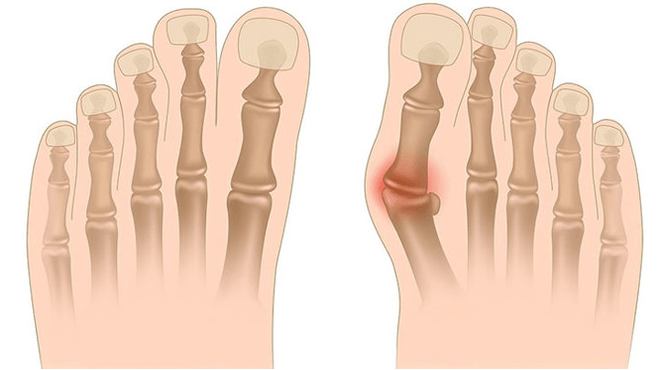

Valgus deformation is the curvature of the foot, characterized by the flattening of its vertical arch.Typically, the inside of the foot is lowered (drops fall), and the heel pops out.

When you take your feet (if you look at them from the back), a deform like X is formed at the ankle level: the ankle contacts, while the heel is at a distance of 5-6 cm from each other.

- I - There is no bone deformation, pain is determined on the inner surface of the ankle (in the area that ties the posterior tibia muscle);

- II - Light curvature, heel is a little rejected;

- III - Foots are allocated and deformed is fixed (not correctly adjusted);

- IV - The curvature is observed not only in the feet, but also in the ankle joint.